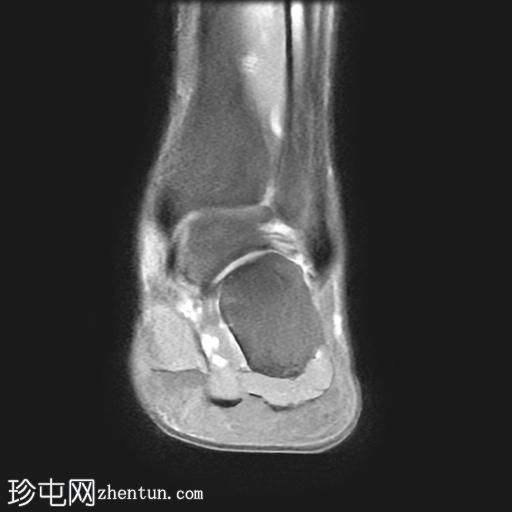

MRI

矢状位

PD脂肪抑制序列

冠状位

T1加权像

冠状位PD脂肪抑制序列

轴位

T2加权像

跟骨前突延长增宽,与舟骨形成不规则关节,形似“食蚁兽

鼻

”。

该异常跟舟关节处可见关节下骨髓水肿。此外,舟骨内外侧径增宽,向外侧逐渐变细,并与增大的跟骨前突形成关节。

距舟关节轻度积液,并可见边缘骨赘。